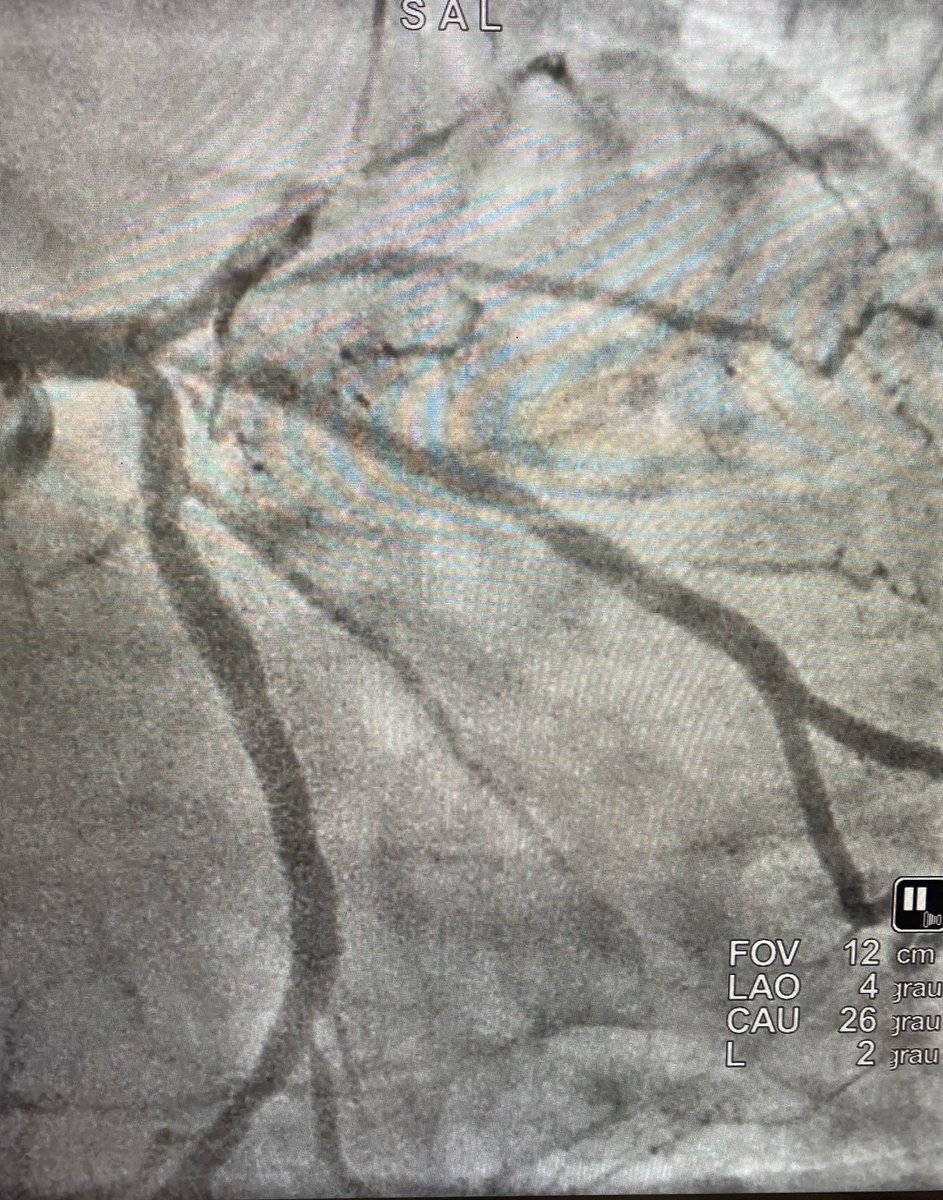

LAD/Dg bifurcation, reverse wire technique Watch on X

LAD/Dg bifurcation Reverse wire IVUS-guided

LAD/Dg bifurcation: Streamline Reverse Wire + mini-crush

True bifurcation lesion with extremely difficult side branch access. Streamline Reverse Wire technique used to gain access to the diagonal, followed by IVUS-guided mini-crush stenting. Demonstrates structured wiring strategies and the role of intracoronary imaging for two-stent bifurcation optimization.

Artery: LAD/Dg

Technique: Reverse wire

Stent strategy: Mini-crush

Imaging: IVUS